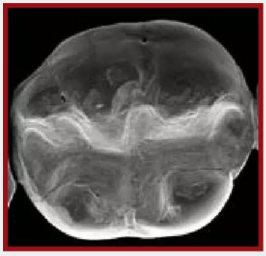

復(fù)合樹脂在即刻充填后,觀察其在電子顯微鏡下的掃描圖像,本次研究選擇了9種具有代表性的復(fù)合樹脂材料。

4.png

Filtek LS 3M ESPE